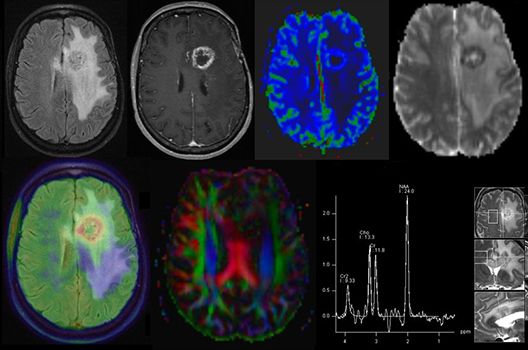

Die Schwerpunkte in der MR-Forschung liegen in der multiparametrischen und funktionellen Bildgebung bei onkologischen und anderen, neuroradiologischen Fragestellungen und umfassen die Anwendung modernster MR-Verfahren sowie die Untersuchung an Hochfeld-Geräten.

Die Magnetresonanztomographie (MRT) ist ein Verfahren, bei dem durch magnetische Kräfte Bilder des Körperinneren angefertigt werden. In der Neuroradiologie können manchmal kleinste Veränderungen schwere Folgen haben; daher forschen wir an der Entwicklung hochauflösender MRT-Sequenzen, mit denen diese Prozesse und auch einzelne Nervenfaserbahnen sichtbar gemacht werden können. Darüber hinaus sind bei vielen Erkrankungen des Gehirns die Blutgefäße betroffen. Daher arbeiten wir an der Neu- und Weiterentwicklung von MRT-Sequenzen zur Darstellung der Blutgefäße und zur Blutflussanalyse (sog. „Angio-MRT“). Einen besonderen Forschungsschwerpunkt unserer Klinik stellen die MR-Protonenspektroskopie und die funktionelle MRT dar, mit denen die Analyse einzelner chemischer Substanzen im Hirngewebe oder die Darstellung ausgewählter Hirnfunktionen möglich ist.

Die Hybridbildgebung mittels PET/MRT spielt insbesondere in der onkologischen Bildgebung eine wichtige Rolle. Eine mögliche Fragestellung ist die Unterscheidung zwischen einem Tumorrezidiv oder therapeutisch assoziierten Veränderungen insbesondere dann, wenn diese Frage mittels MRT alleine nicht beantwortet werden kann.

Die bildgebende Diagnostik und Verlaufsbeurteilung von Tumoren des Nervensystems ist einer der klinischen und Forschungsschwerpunkte unserer Abteilung. Eine besondere Bedeutung kommt der Hybrid-Bildgebung zu. Das Universitätsklinikum verfügt über einen integrierten Ganzkörper-PET/MRT-Scanner, der die Vorteile der MRT-Bildgebung und der Positronenemissionstherapie (PET) vereinigt. Aufgrund der langjährigen klinischen Arbeit und Forschungstätigkeit mit diesem Gerät hat die Neuroradiologie Tübingen maßgeblich zur Etablierung dieses Verfahrens beigetragen. Auch weiterhin forschen wir intensiv an neuen Methoden zur frühen Einordnung von Tumoren und insbesondere Tumorrezidiven, die mit anderen Methoden häufig nicht erfasst werden können.